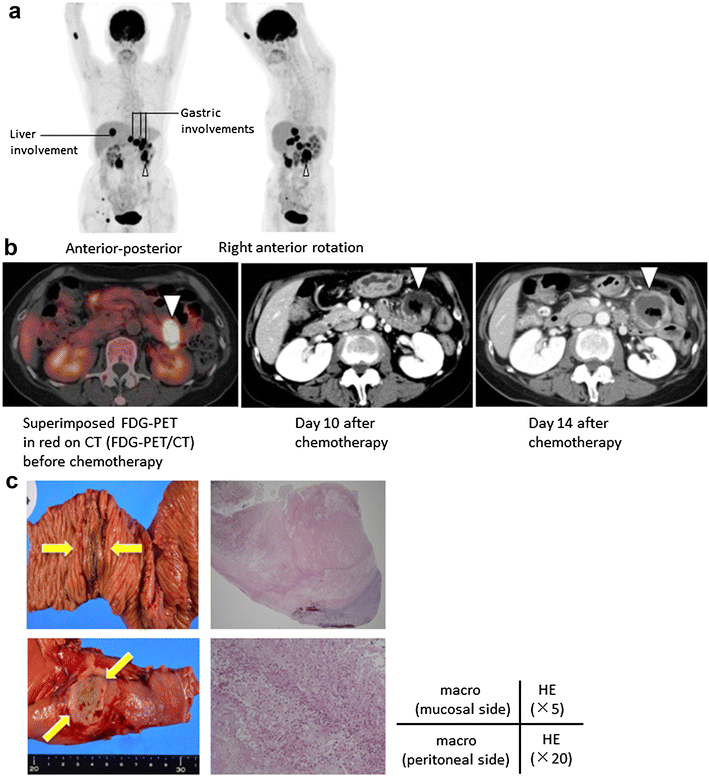

Case presentation: The 61-year-old female patient had a history of primary central nervous system lymphoma (PCNSL), diagnosed histologically as diffuse large B cell lymphoma (DLBCL). We administered six courses of intensive chemotherapy consisting of high-dose methotrexate and sequential whole-brain irradiation (40.5 Gy). After a 3-year remission of the PCNSL, the patient's lymphoma recurred, involving the small intestine. (18)F-FDG-PET/CT upon the recurrence before chemotherapy showed multiple nodular lesions in the patient's gastrointestinal tract. Central nervous system lesions were not detected. We administered intensive salvage chemotherapy consisting of cyclophosphamide, high-dose AraC, methyl-prednisolone, etoposide, and rituximab. The response was a rapid partial response, but on day 10 after the initiation of salvage chemotherapy, she complained of abdominal pain with tenderness. The contrast-enhanced (CE)-CT revealed transmural ischemia of the intestine. On the 7th day after the onset of urgent abdominal symptoms, follow-up CE-CT showed that the ischemic lesion had become thin. We conducted elective surgery after waiting for the complete recovery of the patient's white blood cell count. The pathological findings of resected intestine confirmed the elimination of the majority of lymphoma cells and concomitant partial necrotic tissue.

Conclusions: We were able to avoid the neutropenic period and safely conducted the surgical treatment for the subclinical perforation by using CE-CT. The combination of (18)F-FDG-PET/CT before chemotherapy and CE-CT scanning for the targeted involvement site helped us evaluate the surgical indications and optimal timing of surgery in a lymphoma patient with gastrointestinal involvement.